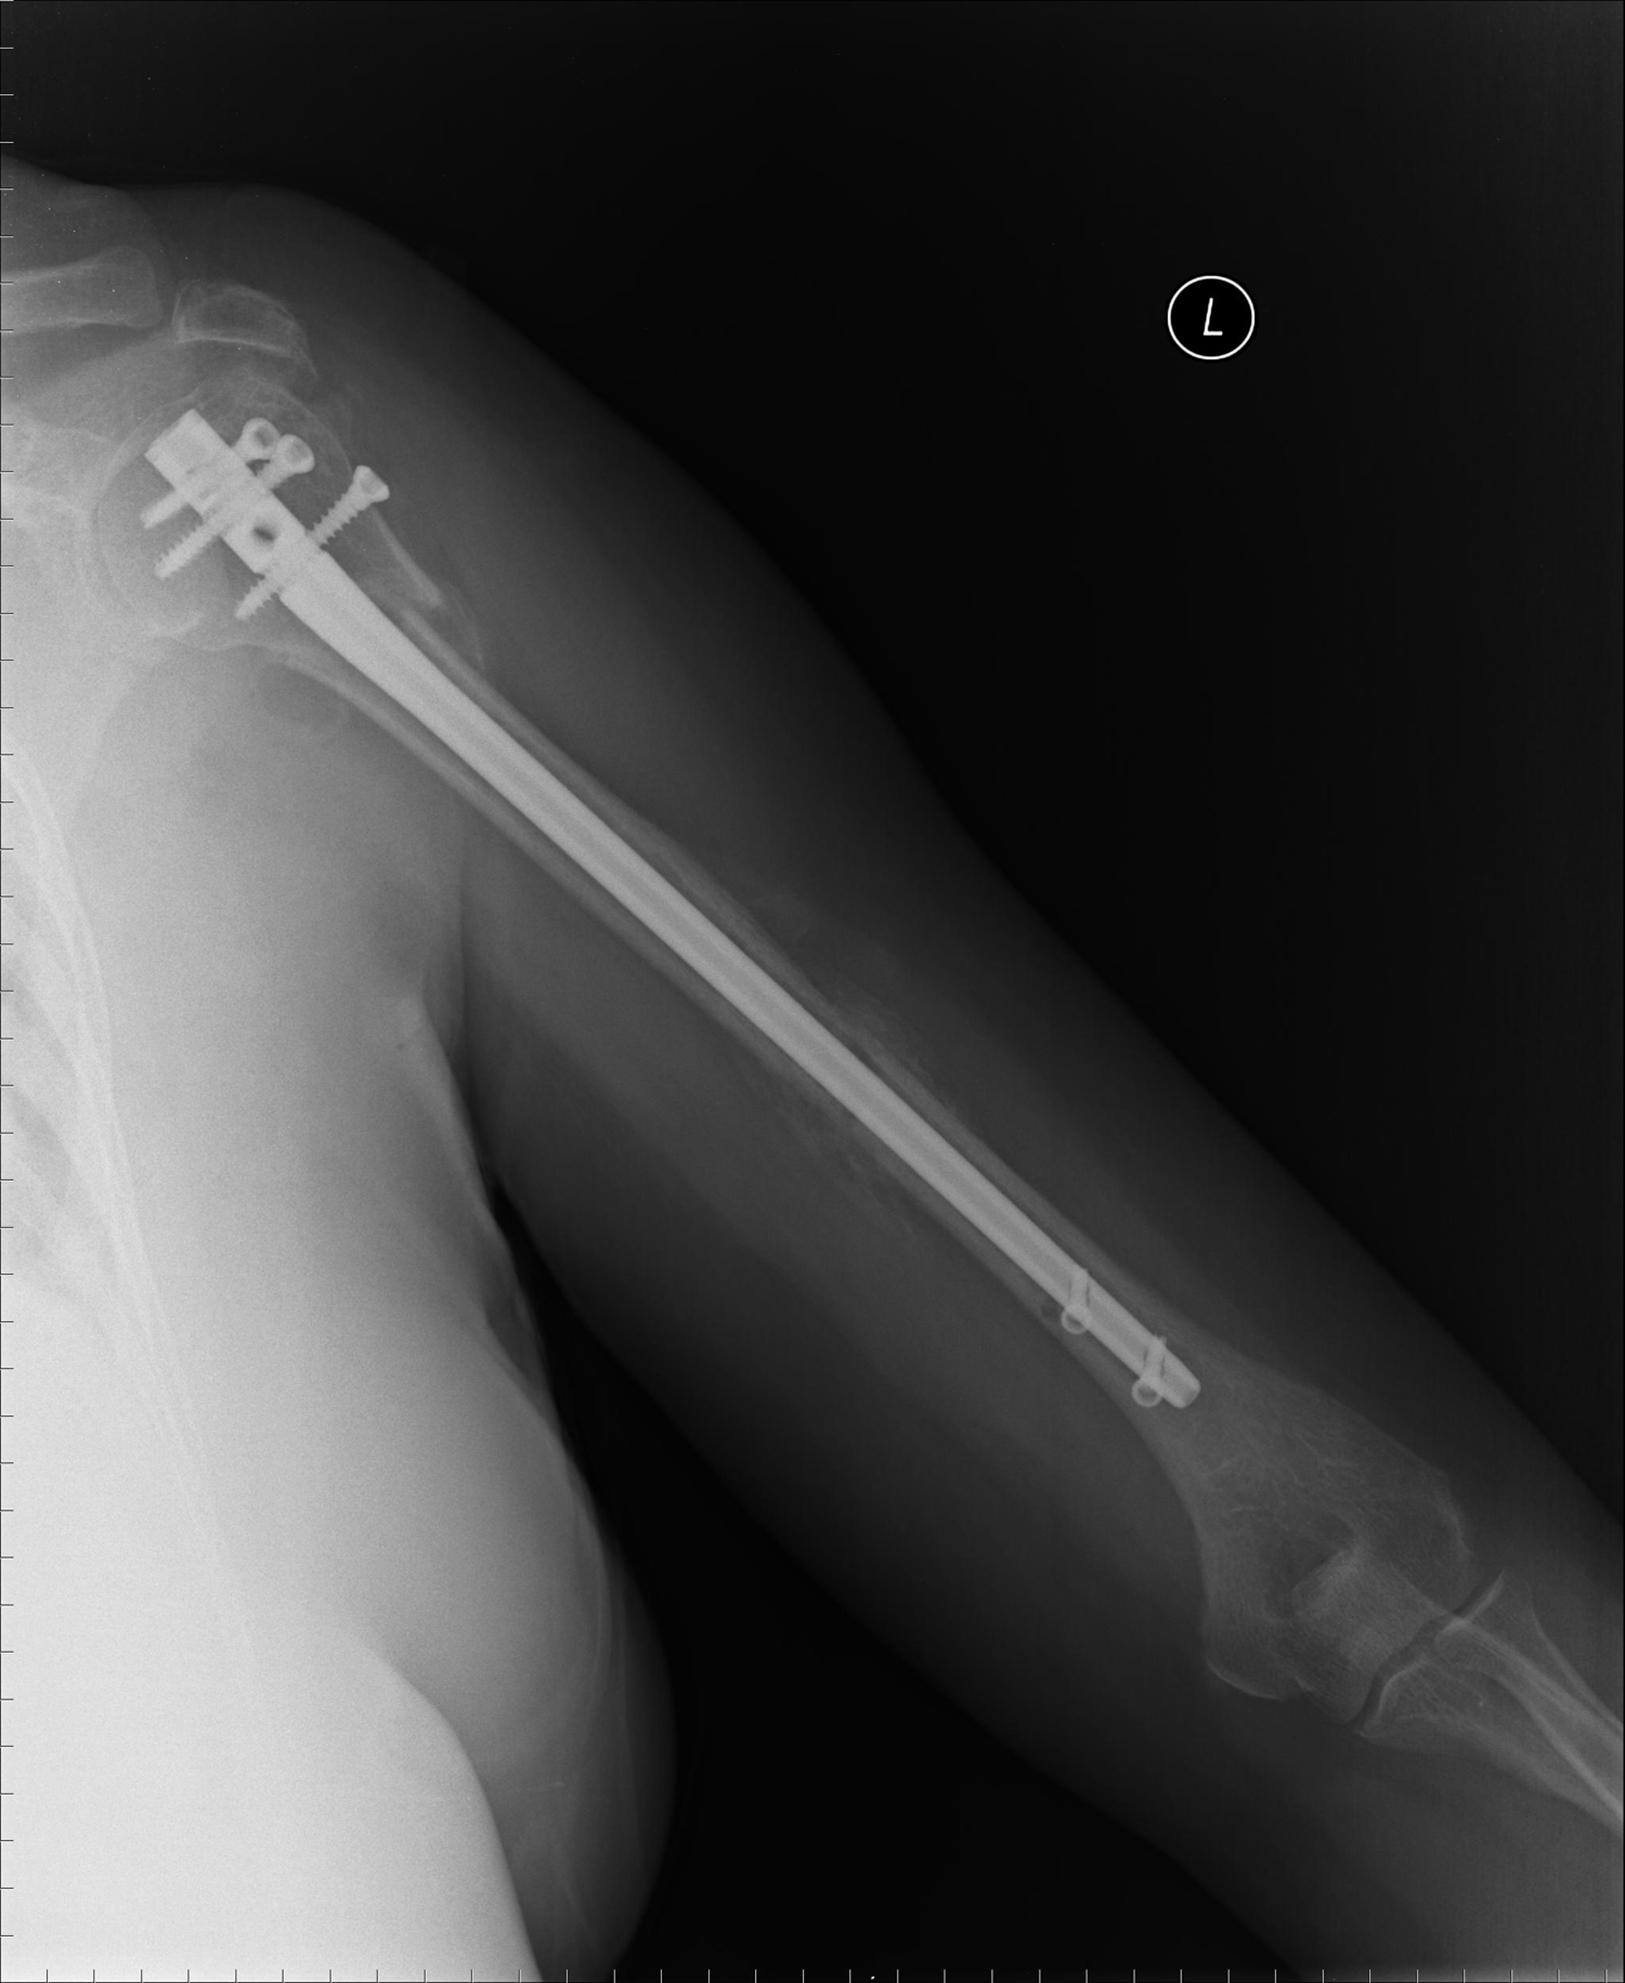

Intramedullary nailing (SEE Technique 57.4) provides more stable fixation than percutaneous pinning, although less than locked plate fixation. The Polarus nail (Accumed, Portland, OR) has been shown to provide more biomechanical stability than pin fixation, and good clinical outcomes have been reported with this device. Newer nail designs with polyaxial screws have more stability than earlier designs, and the addition of polyethylene bushings may increase stability and prevent screw back-out ( Fig. 57.27 ). Insertion of an intramedullary nail into the proximal humerus violates the rotator cuff, which can lead to postoperative shoulder pain. The advantages of the technique include preservation of the soft tissues and the theoretical biomechanical properties of intramedullary nails. A comminuted lateral cortex fracture or fractures involving the tuberosities may be a contraindication to intramedullary nailing. A recent randomized controlled trial demonstrated that complications were fewer with a straight nail design compared with a curvilinear design. A systematic review by Wong et al. reported satisfactory results in displaced two- and three-part proximal humeral fracture treatment with intramedullary nails. Sun et al. compared locking plates with intramedullary nails in displaced proximal humeral fractures in a systematic review and meta-analysis and demonstrated similar performance between the two fixation types.

FIGURE 57.27, Fixation of segmental proximal humeral fracture with locked intramedullary nail.

• Two-part surgical neck fractures with displacement do poorly with nonoperative treatment. Closed reduction and percutaneous pinning have been reported to be successful in fractures that are reducible and are not comminuted. Complications such as loss of fixation, pin migration, infection, and malunion have made rigid intramedullary nailing our preferred technique, however, for fractures that can be reduced closed and for segmental fractures (see Fig. 57.27 ). The violation of the rotator cuff is offset by the advantages of decreased soft-tissue violation and decreased blood loss compared with ORIF. Widely displaced fractures, fractures with comminution, and irreducible fractures are stabilized with a locked-plate construct (see Fig. 57.28 ). Improved proximal fixation of these systems has increased stability so that immediate postoperative range of motion is allowed. For extremely osteopenic patients, Banco et al. described a “parachute” technique, which included a valgus impaction osteotomy and tension-band fixation incorporating transosseous sutures ( Fig. 57.32 ). Union was obtained in all 14 elderly patients, and patient satisfaction and function were excellent.